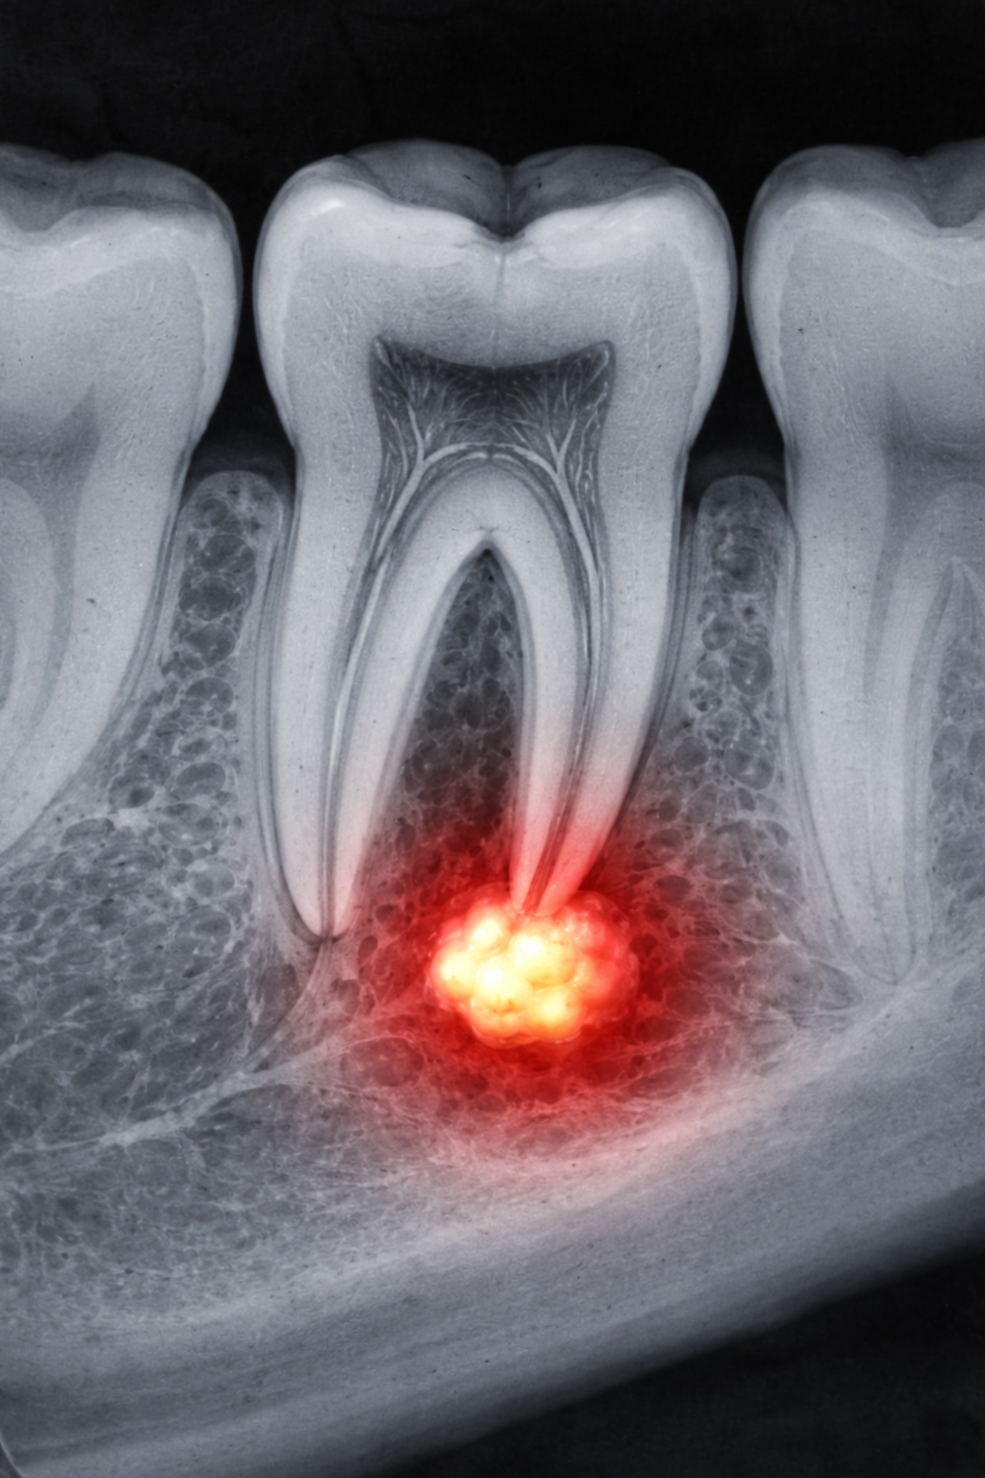

The most common situation where we see a dental abscess is when tooth decay gets too deep and reaches the nerve at the center of a tooth. Once bacteria reach that space, the body can’t clear the infection on its own. The infection travels down the inside of the tooth, exits at the tip of the root, and the body responds by forming pus at the end of the tooth. That’s what we call a dental abscess.

In many cases, abscesses are painful. Patients may feel throbbing, pressure, or pain when biting. Swelling or tenderness in the gum or face can also occur. But one of the most important things to understand is this: sometimes there are no symptoms at all. The tooth may stop hurting, or it may never have hurt in the first place. That doesn’t mean the infection is gone—it often just means pressure has temporarily relieved itself. This is why abscesses can be easy to miss without an exam and imaging.